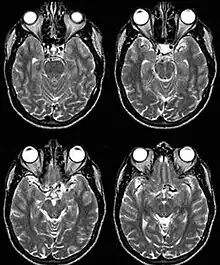

Internal carotid artery dolichoectasia is particularly interesting because the artery normally already contains one hairpin turn. Seen in an MRI as two individual arteries at this hairpin, a carotid artery dolichoectasia can progress so far as to produce a second hairpin turn and appear as three individual arteries on an MRI. In the case of a dolichoectasia of the Internal Carotid Artery (ICD), the pathogenesis is primarily related to compression of the optic nerves at the optic chiasma (see Fig. 1 and 2).